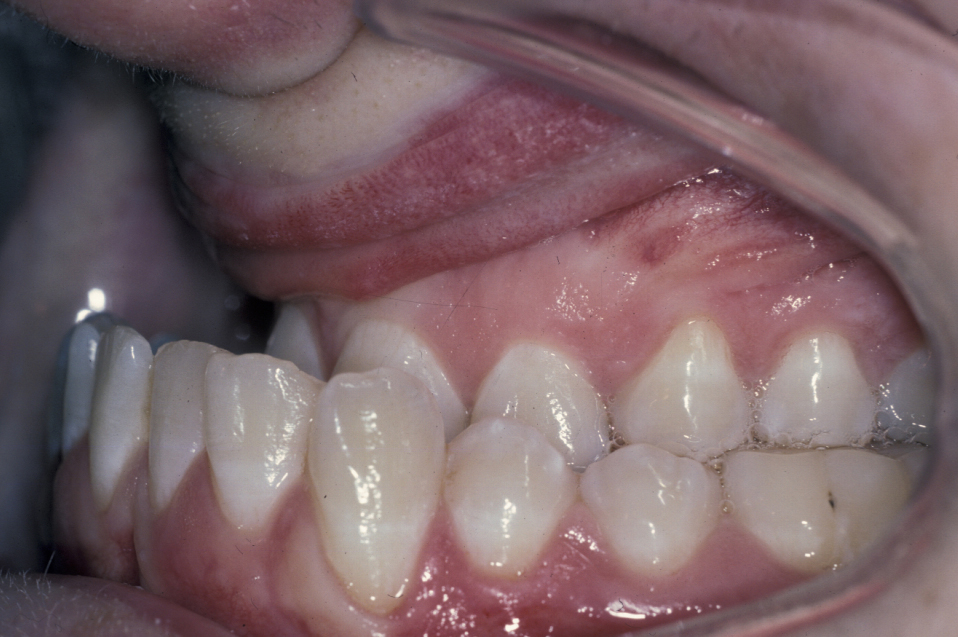

The molar and incisal relationships are examined visually and are formally documented by photographs (see Figure 5, Figure 6 and Figure 7 for examples) and study models (see below).

Figure 5: Intraoral view showing a class III malocclusion (underbite).

Figure 6: Intraoral view showing a class III malocclusion (underbite).

Figure 7: Intraoral view of a class III malocclusion (underbite).